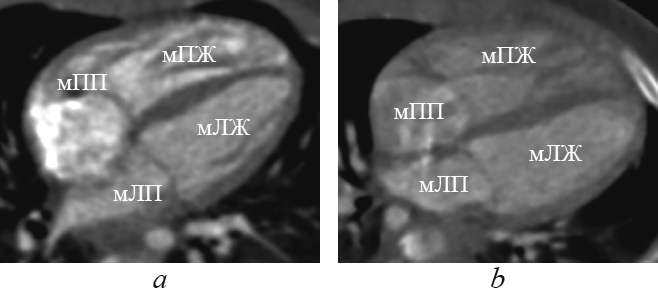

This article contents the results of computed tomography with intravenous bolus contrast media administration data analysis in children with transposition and congenitally corrected transposition of the great arteries with the consequental performing of the multiplanar heart-axis-oriented reformations. Among 148 examined children transposition of great arteries was detected in 13 patients (9 boys and 4 girls aged 1-144 day of life); congenitally corrected transposition was found in 4 cases of children aged from 6 months to 15 years and 6 months (2 boys and 2 girls). In this article comprehensive anatomical criteria of each heart chamber morphology are presented and reformations where these criteria can be seen are shown. Also in the article is given comparative characterization of heart and great arteries structures in transposition and congenitally corrected transposition in every certain heart-axis-oriented reformation. By the results of consequently performed heart-axis-oriented reformations data analysis the peculiar anatomical signs of transposition and congenitally corrected transposition are determined. The results of data analysis show that from the list of offered reformations the peculiar anatomical signs of both kinds of transposition are significantly determined in long-axis of right ventricle inflow tract reformation, left heart chambers reformation, supply ventricle division reformation, short-axis reformation at the level of great arteries. Computed tomographic angiocardiography heart-axis-oriented multiplanar reformations permit full and correct assessment of heart and main vessels, which is important for planning of surgical treatment in congenital heart diseases.